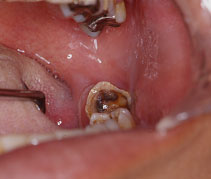

齲蝕症や辺縁性歯周炎、さらに、智歯周囲炎は、ほとんどが口腔内常在菌などの細菌によって発症する歯性の感染症であり、主に化膿性炎症を生じます。これらは緩慢に経過するが、

しばしば激烈な急性経過をたどり、急性化膿性顎骨骨膜炎や広範な蜂窩織炎へと進展することがあります。

虫歯(う蝕症)、歯槽膿漏(歯周炎)

歯髄感染症(化膿性歯髄炎)

根管内感染

根尖性歯周炎→顎骨骨髄炎

歯槽骨炎→歯槽膿瘍

顎骨骨膜炎+顎下隙膿瘍や顎骨骨膜炎+眼窩周囲膿瘍